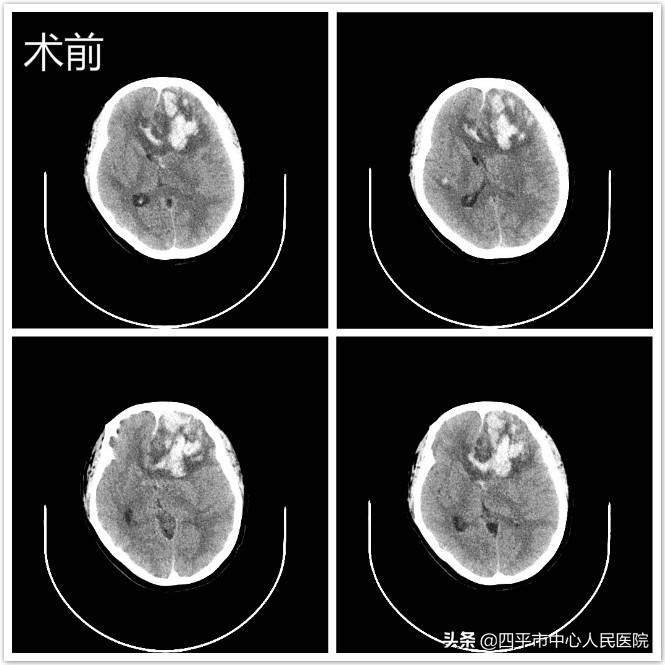

2019年12月神经外科收治一位白血病继发脑出血昏迷血小板严重低下患者。该患者中年女性,急诊查头部CT发现左侧额叶脑出血,周围伴有脑水肿,中线结构明显向右侧移位。血小板13X10^9/L。

李主任术前做了充分的预案:术中输血小板1单位和血浆400毫升,准备自体血回输,去骨瓣减压(可能出现迟发性出血)。开颅手术过程中,从开头皮,锯骨瓣,剪硬脑膜,清除脑内血肿及关颅整个手术过程中,创面都渗血,好在有自体血回输;术中发现脑组织明显肿胀,尽管如此,李主任在显微镜下将左侧额叶脑内血肿彻底清除,颅内压下降,彻底止血后关颅。调整体位完成气管切开术后安返病房。术后CT显示左侧额叶脑组织略有渗血,但减压窗张力不高,达到减压目的。